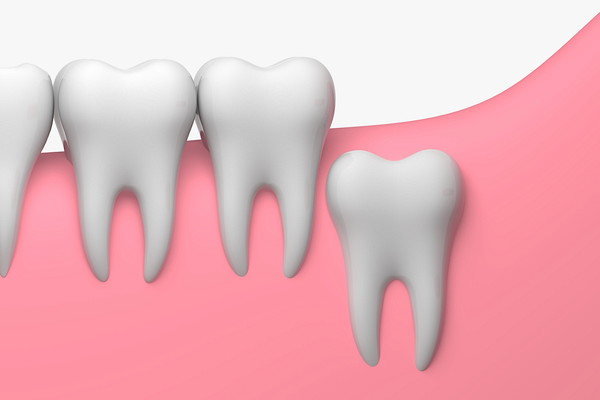

完全に横に倒れているタイプ

歯ぐきの中に横に倒れ、完全に埋まっているタイプは目で確認することができません。

歯の部分が出ていないため、虫歯や歯周病になるリスクはありませんが、顎の骨の中に嚢胞(袋状の空砲)を作り、歯を圧迫するといったトラブルの原因になることがあります。

また、手前の歯に倒れているタイプだけでなく、さらに奥を向いて生えている「逆性埋没智歯」もあります。

歯ぐきが腫れるといった痛みが出た場合には、歯ぐきの中で親知らずが生えている可能性があります。

レントゲン写真を撮影すると、歯ぐきの中の状態も確認することができるため、親知らずをどのように治療するか検討できます。

痛みや腫れがある場合には早めに受診して相談しましょう。